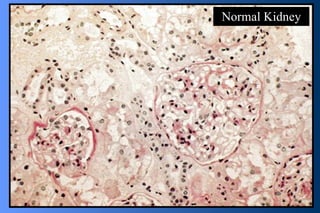

Normal Kidney

Microthrombi PMN’s Hyperacute Rejection